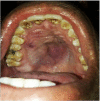

Dentigerous cyst is one of the most common developmental cyst of the jaw which accounts for approximately 20%-30% of bone cyst in the head and neck region. Most common site is the third molar of the mandible. However, maxillary involvement is not uncommon. The clinical presentation of this depends mainly on the size and anatomical compromise that occur due to compression. This case highlights the role of endoscopic approach in the management of large expansible cyst of maxilla involving the palate, thus preserving the anatomy and reducing the morbidity associated with an open procedure.